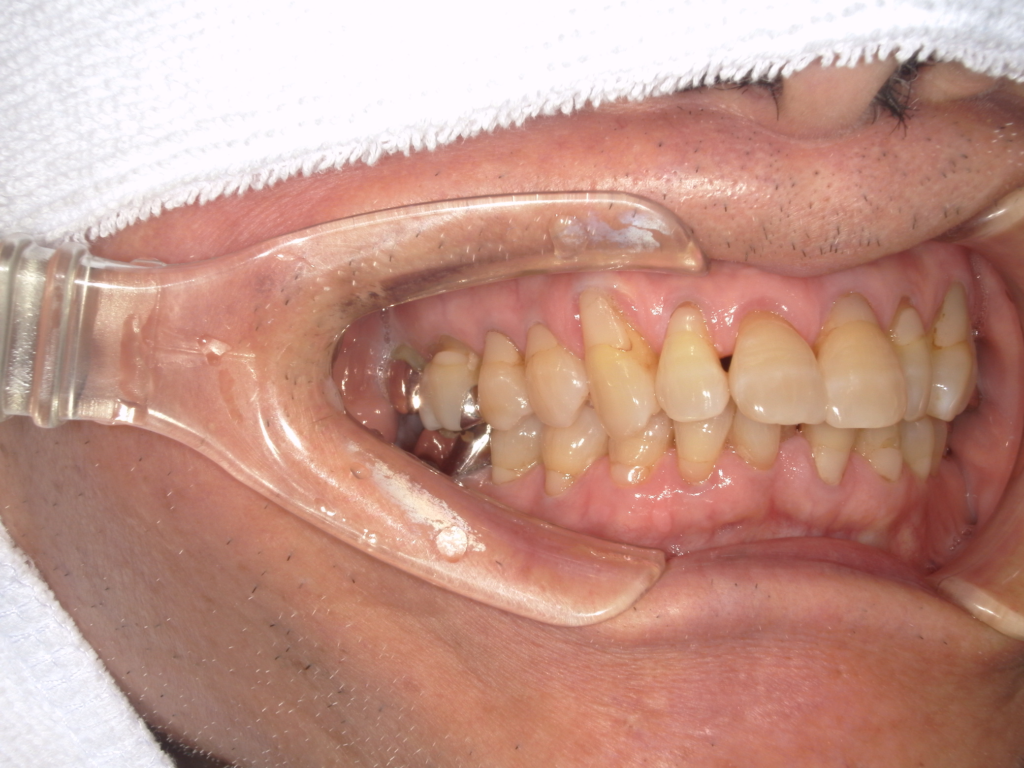

Y様インプラント実例 #44

左の上下の奥歯をインプラントで治療しています。

左下の奥歯は歯を抜くのと同時にインプラントの埋め込みを行っています。

被せものは上下、セラミックスで作っています。

治療前

治療後